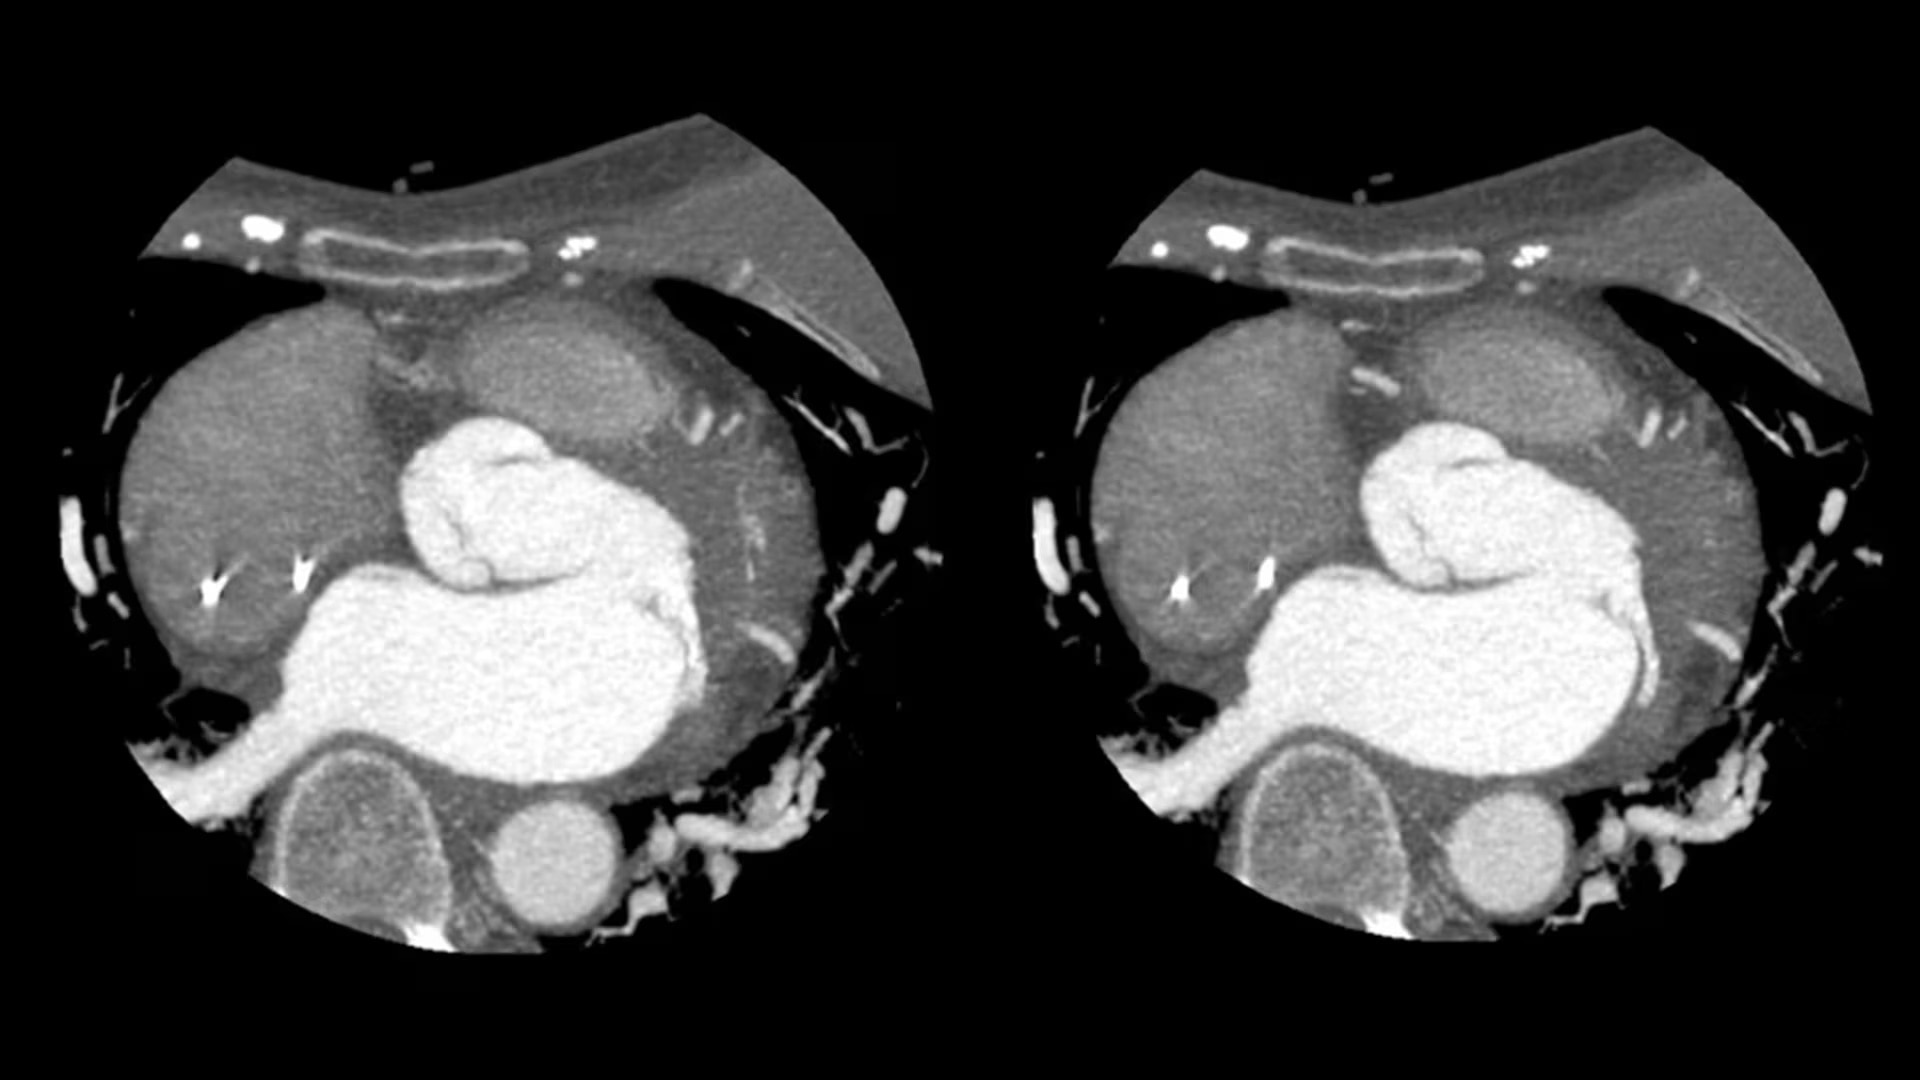

SnapShot Freeze 2

Intelligent and automated whole-heart motion correction for enhanced Cardiac CT imaging.

Temporal resolution

19.5 msec effective temporal resolution at 0.23s/rotation gantry speed2